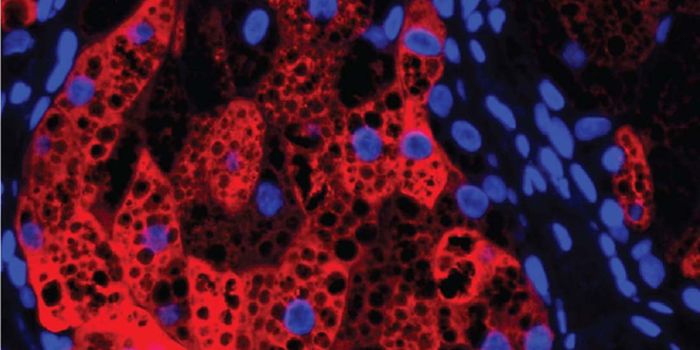

MAR 22, 2021ImmunologyImmunologists have identified a mechanism through which an oncogene mutation shields pancreatic tumors from immune cells ...